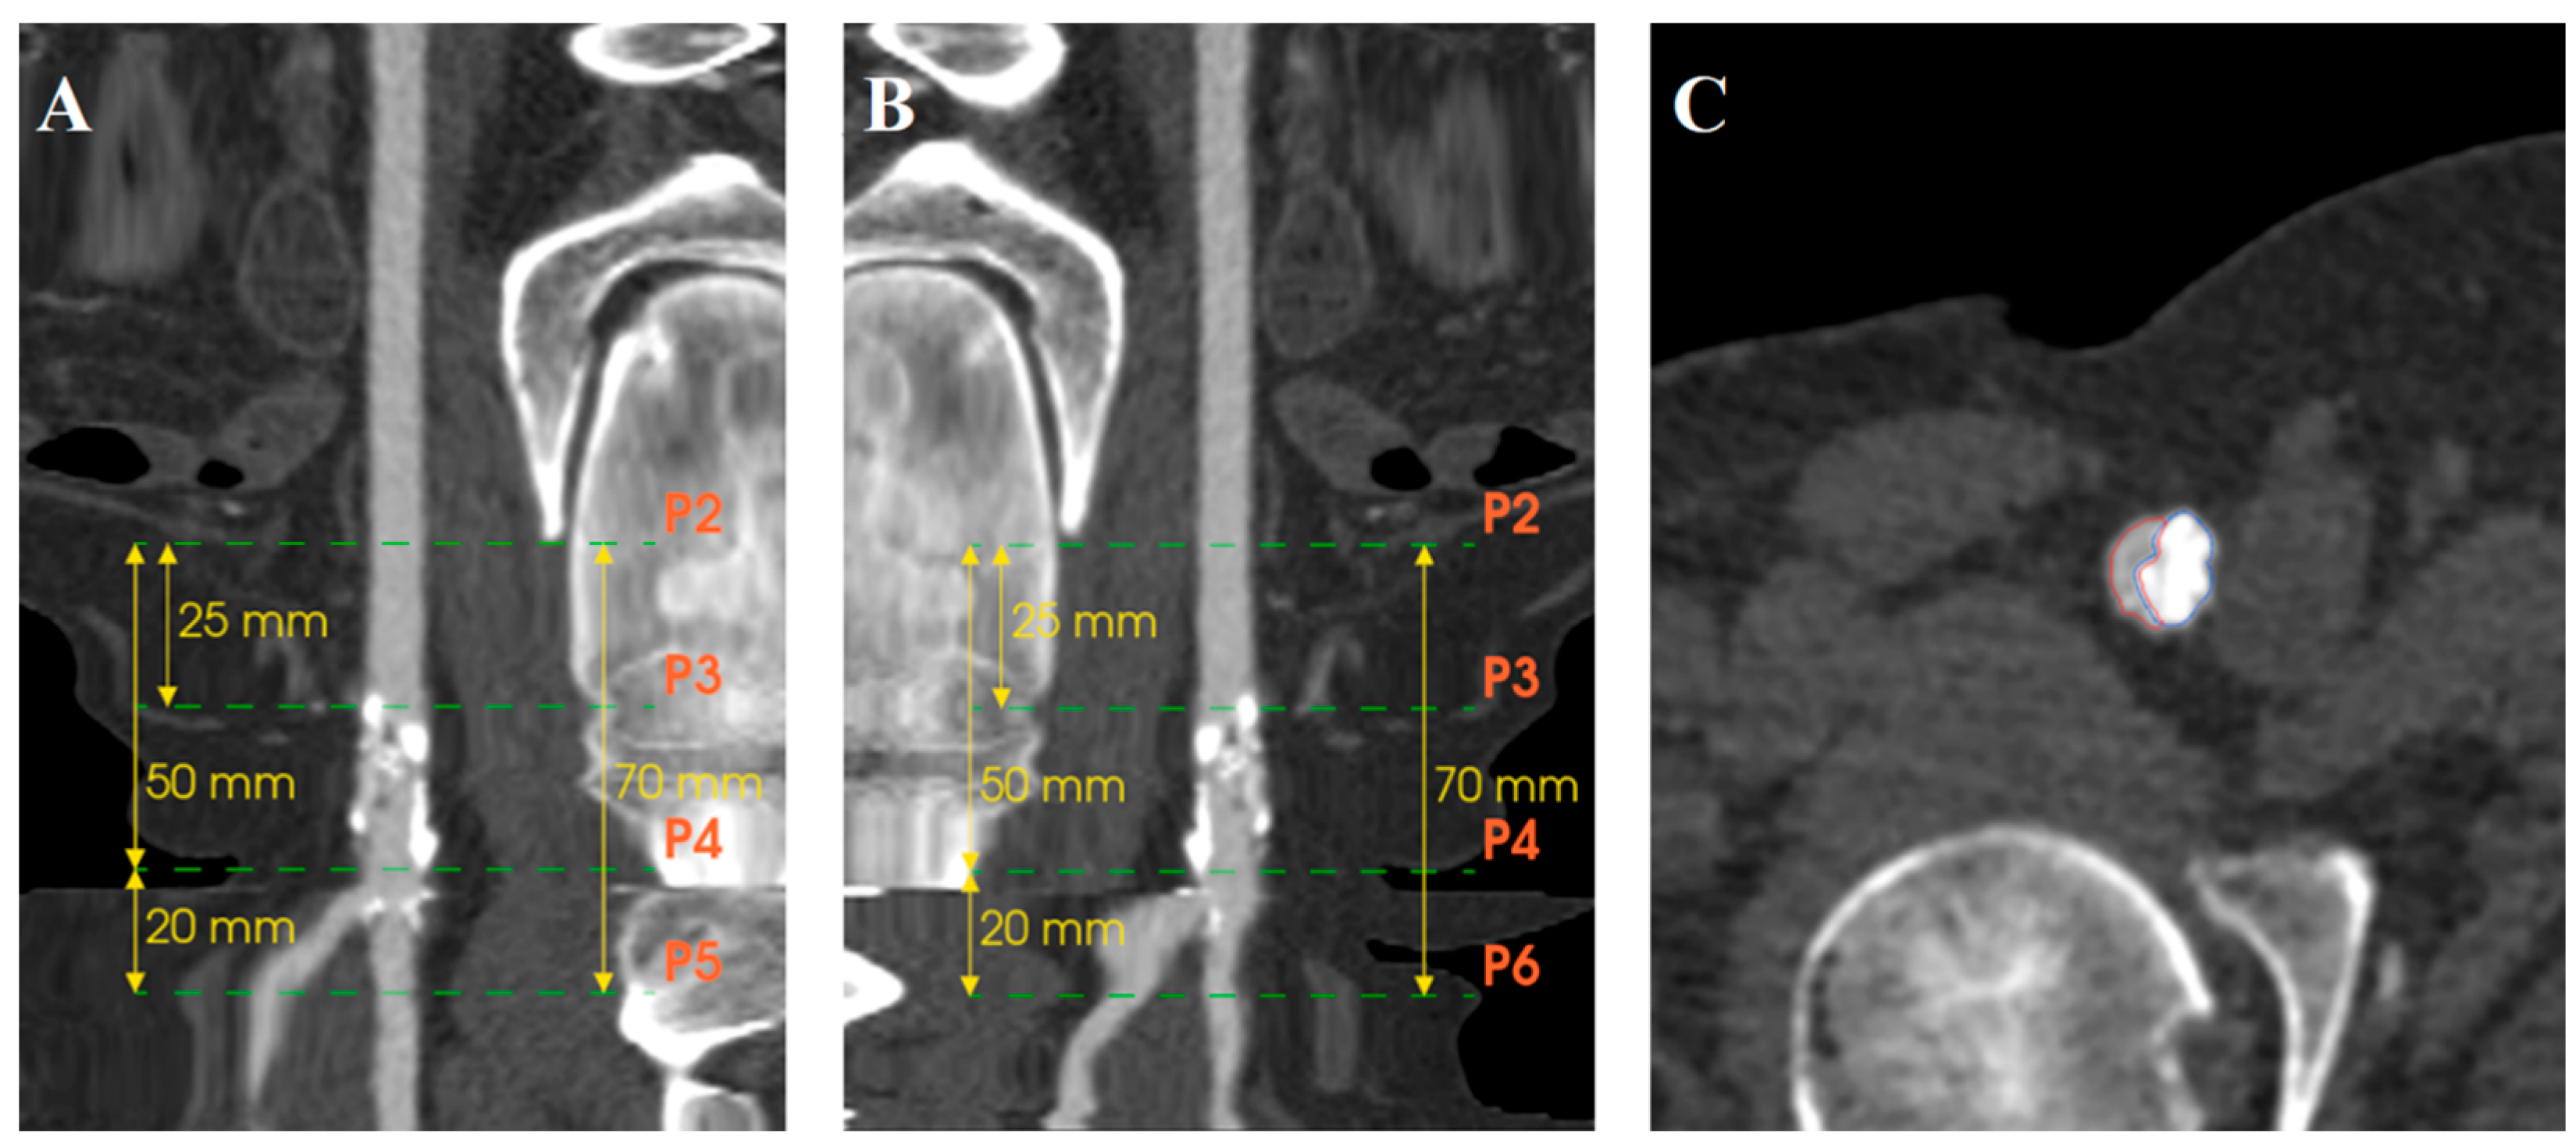

Computed tomography angiography (CTA) images were retrospectively analyzed using EndoSize software (Therenva, Rennes, France) with a specially developed calcification assessment tool that provided automated measurements through an algorithm differentiating true arterial lumen from calcifications, considering scanner energy parameters and contrast injection density. Briefly, the software creates a region of interest as a tubular structure along extracted centerlines within the arterial lumen. The calcification detection threshold is automatically calculated as the mean Hounsfield Unit (HU) value of voxels surrounding the centerline plus a delta value derived from the standard deviation, establishing a patient-specific threshold that accounts for individual scanner parameters and contrast injection characteristics. This automatically calculated threshold remains adjustable by the operator to optimize calcification detection accuracy. The calcification assessment investigators were blinded to the outcomes. Inter-observer reproducibility was assessed by two independent operators. The intraclass correlation coefficient (ICC) demonstrated good inter-observer agreement for calcification density measurements (ICC = 0.84, 95% CI: 0.71–0.92) and moderate-to-good agreement for volume measurements (ICC = 0.78, 95% CI: 0.62–0.88).The CFA bifurcation was defined as the arterial segment running between the epigastric artery (proximal limit) and two cm after the ostia of the DFA and SFA. Two centerlines were extracted, one from the CFA above the DFA and the other above the SFA. Different points were placed on the centerline (Figure 1). P2 was located at the level of the epigastric artery, P3 midway between the epigastric artery and femoral bifurcation, P4 at the CFA bifurcation, P5 two cm after the ostium of the DFA, and P6 two cm after the ostium of the SFA (Figure 2A,B). Segmentation of the arterial lumen and calcification volume were obtained manually (Figure 2C).

Three zones were defined: Zone 1 proximal CFA (P2–P3), Zone 2 distal CFA (P3–P4), and Zone 3 CFA bifurcation and the ostia segments of the SFA/DFA (P4–P5/P6) (Figure 3). Segmentation of the arterial lumen and calcification volume were obtained manually. For each zone, the minimum, maximum, and median densities (Hounsfield Unit [HU]) and calcification volumes (mm3) were measured on preoperative CTA.

Figure 2. Centerlines and point placements. (A) Stretching of the centerline above the DFA. (B) Stretching of the centerline above the SFA. (C) Centerline analysis of true lumen (red area) and calcifications (blue area).